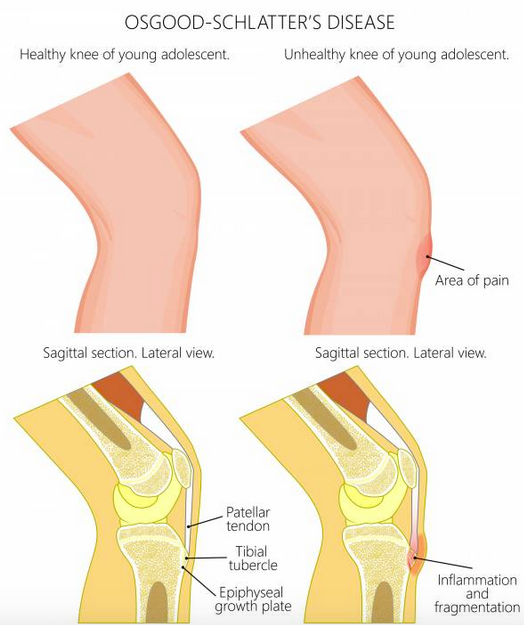

3. As ‘n groeiende en sportief-aktiewe kind kla van knie- of onderbeenpyn, kan dit moontlik Osgood-Schlatter sindroom wees waar die ligament wat die knieskyf vashou, en wat aan die onderbeen vasheg, so sterk trek dat dit ‘n deel van die onderbeen laat af-brokkel.